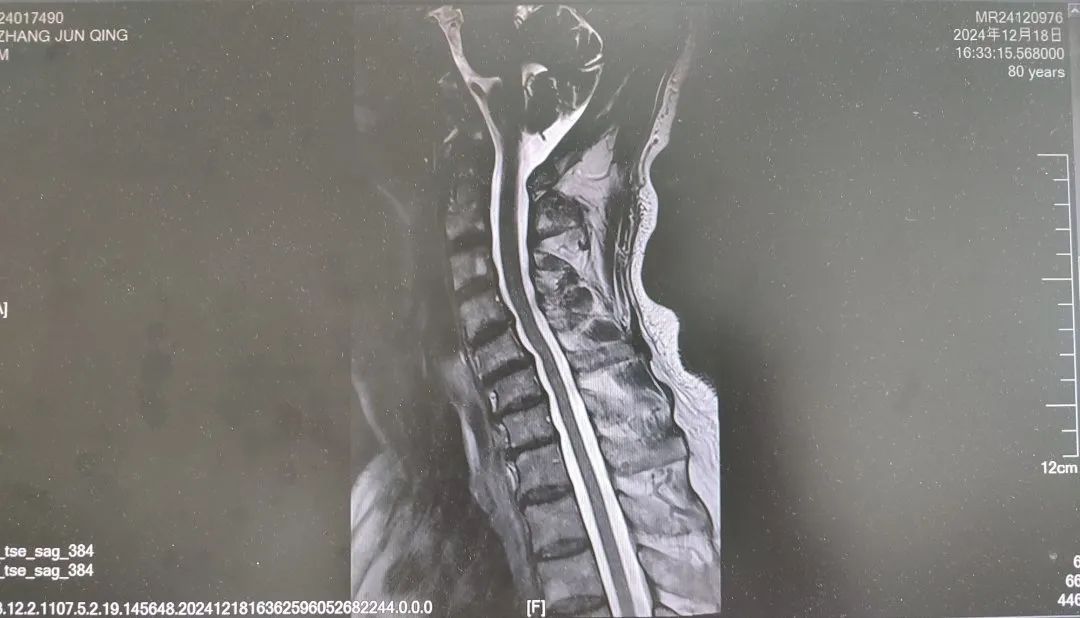

內(nèi)容提要 很多人都想擁有纖細(xì)、健美的雙腿,嘗試多種健身方法,效果卻始終不理想。然而社會(huì)上大約有萬分之四的人,他們不用減肥,雙腿就會(huì)慢慢“瘦”下來,如倒置的香檳酒瓶,醫(yī)學(xué)中稱之為“鶴腿”。不過這并非自愿,而是源于一種名為“腓骨肌萎縮癥”的罕見疾病。近日,市二院神經(jīng)內(nèi)二科趙智江主任團(tuán)隊(duì)就幫助一位受腓骨肌萎縮癥困擾4年之久的患者明確了病因。 #01 “鶴腿”多年不明病因 竟是罕見病作祟 患者80歲,四年前無明顯誘因出現(xiàn)步態(tài)異常,行走困難,起初以為是勞累所致,并未過多在意。然而,近一年來癥狀逐漸加重,雙下肢膝關(guān)節(jié)以下麻木、發(fā)涼,行走時(shí)右下肢有甩腳動(dòng)作,呈跨閾步態(tài),右足趾背屈不能,同時(shí)存在站立不穩(wěn)、不能蹲下等癥狀,嚴(yán)重影響日常行走。這一年間,他輾轉(zhuǎn)市內(nèi)多家醫(yī)院,經(jīng)歷了無數(shù)次的檢查和咨詢,卻始終未能得到確切診斷。 近日,患者經(jīng)多方打聽,來到了以診治神經(jīng)疑難病為特色的市二院神經(jīng)內(nèi)二科。入院后,趙智江主任為患者進(jìn)行了細(xì)致入微的查體,發(fā)現(xiàn)患者雙側(cè)大腿下三分之一處及小腿肌肉萎縮。進(jìn)一步完善頭顱、頸椎及胸椎核磁的檢查,由于患者存在跨閾步態(tài),結(jié)合檢查結(jié)果,初步考慮為腓總神經(jīng)麻痹。 頭顱、頸椎核磁回報(bào)后,基本上排除了神經(jīng)根的疾病和脊髓疾病。肌電圖結(jié)果提示四肢周圍神經(jīng)受累,右側(cè)腓總神經(jīng)損傷更重,修正診斷為周圍神經(jīng)病。然而,周圍神經(jīng)病存在多種病因,需進(jìn)一步查找病因。趙智江主任結(jié)合患者雙下肢肌肉萎縮情況,排除其它病因?qū)е碌闹車窠?jīng)病,最終明確診斷為腓骨肌萎縮癥。 頭顱核磁影像 頸椎及腰椎核磁影像 隨后,中國醫(yī)科大學(xué)附屬第一醫(yī)院神經(jīng)內(nèi)科著名專家何志義教授及遼寧名醫(yī)、市二院卒中中心主任閔連秋教授在查房時(shí)同樣肯定了腓骨肌萎縮癥的診斷。 腓骨肌萎縮癥是一組具有高度臨床和遺傳異質(zhì)性的周圍神經(jīng)單基因遺傳病,以慢性進(jìn)行性四肢遠(yuǎn)端肌無力肌萎縮、末梢型感覺障礙、腱反射減退或消失和高弓足等骨骼畸形為主要臨床特征,多為兒童和青少年期起病。該患者老年起病,極為罕見!目前,腓骨肌萎縮癥無特效治療藥物,主要以支持治療為主。今后,患者只要在康復(fù)醫(yī)師的指導(dǎo)下,根據(jù)神經(jīng)損害范圍進(jìn)行合理的康復(fù)鍛煉,就能保持較好的活動(dòng)能力,提高生活質(zhì)量。 市二院神經(jīng)內(nèi)二科趙智江主任團(tuán)隊(duì)擁有豐富的神經(jīng)系統(tǒng)疑難疾病診治能力,曾幫助大量飽受罕見病困擾多年的患者明確了診斷。隨著診療水平的持續(xù)精進(jìn),神經(jīng)內(nèi)二科將為更多患者提供精確診斷及治療,為更多的神經(jīng)疑難疾病明確診斷,為患者帶來福音。 #02 人民醫(yī)院 人民名醫(yī) 趙智江 主任醫(yī)師 副教授 ·葫蘆島市第二人民醫(yī)院神經(jīng)內(nèi)二科主任 ·中國卒中學(xué)會(huì)高級(jí)會(huì)員 ·中國老年保健醫(yī)學(xué)研究會(huì)老年腦血管病分會(huì)委員 ·北京神經(jīng)內(nèi)科學(xué)會(huì)腦小血管病學(xué)會(huì)委員 ·安徽醫(yī)藥雜志審稿專家 專業(yè)特色:以腦血管病為核心研究方向,擅長各類神經(jīng)系統(tǒng)疾病的診療,尤其在腦血管病、帕金森綜合征、頭暈、頭痛、癲癇、重癥肌無力以及中樞神經(jīng)系統(tǒng)脫髓鞘等神經(jīng)系統(tǒng)疑難、危重疾病的診療方面積累了豐富的臨床經(jīng)驗(yàn)。主持多項(xiàng)重要科研項(xiàng)目,并將最新的科研成果應(yīng)用于臨床實(shí)踐,撰寫十余篇論文著作。